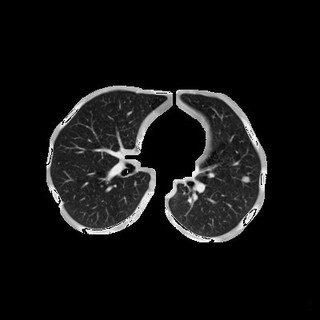

3.设计的代码可以保存每一步的分割步骤图片,最后的分割结果为这样(这两张图片不是同一张图)